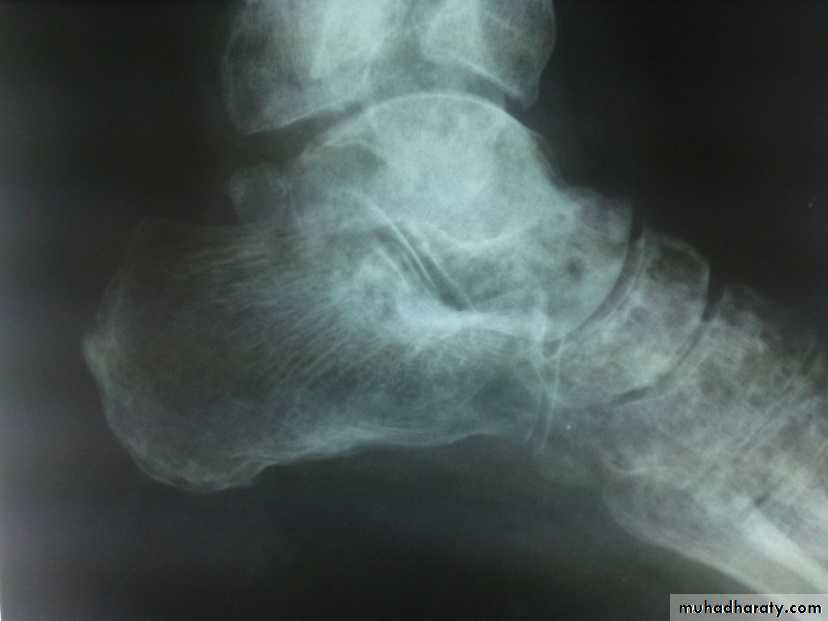

Calcaneal fractures

Usually after FFH.Associated injuries: spine, pelvis, hip or base of skull.

Extra-articular fractures: need closed treatment. Have good prognosis.

Intra-articular fractures:

involve superior articular surface. May be comminuted.

Special features

Foot painful, swollen, bruised and the heel look broad. Movement is painful.Signs of compartment syndrome: intense pain and diminished sensation.

Necessary to X-ray the knees, spine, and pelvis.

Treatment

Admit to hospital, elevate the leg and apply ice-packs until swelling subside.

Undisplaced fractures: closed treatment.

Displaced fractures: ORIF with screws.

Complications

Broadening of the heel

Talocalcaneal stiffness and OA